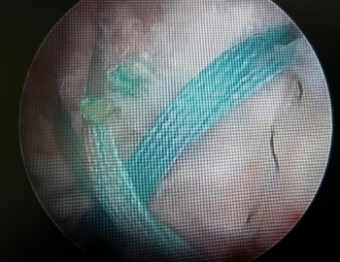

疼痛が強く挙上困難な腱板断裂に対して関節鏡下腱板縫合術(ARCR)を行っています。これにより関節切開で行う従来法と比較し低侵襲で疼痛も少なく早期機能回復が可能となりました。比較的軽微な断裂やインピンジメント症候群に対しては関節鏡下肩峰形成術(ASD)を行い早期社会復帰を目指します。

c.腱板断裂 d.鏡視下縫合後